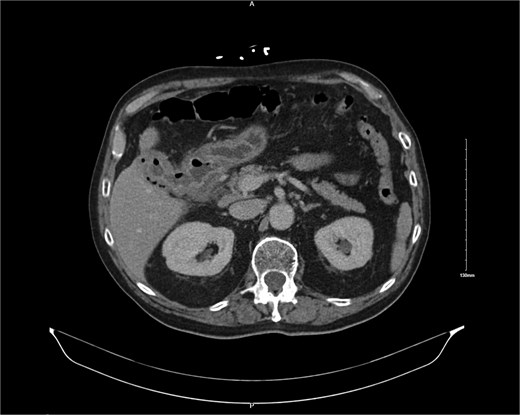

A 76-year-old male with coronary artery disease, diastolic heart failure, atrial fibrillation on apixaban, type 2 diabetes mellitus, and chronic kidney disease presented with acute cholecystitis. Imaging revealed emphysematous cholecystitis with a suspected cholecystoduodenal fistula (Fig. 1). Cardiac workup revealed reduced EF (35%–40%) with no obstructive coronary artery disease. He was treated non-operatively with antibiotics and discharged for interval cholecystectomy.

CT image showing cholocystoduodenal fistula at initial presentation.